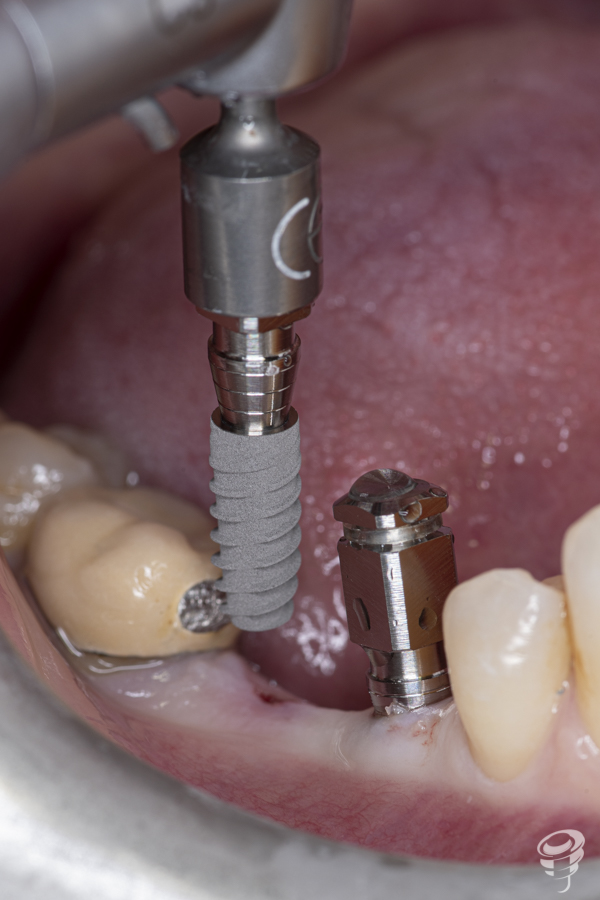

Una vez realizada la planificación de los dos implantes, se lleva a cabo la impresión de la férula quirúrgica dento-soportada con dos orificios cilíndricos adaptados a la fresa pin de 2 milímetros de diámetro. Esta fresa tiene la función de guiar tridimensionalmente la posición del implante.

A posteriori, se retira la guía quirúrgica y se realiza el fresado con la fresa Stop de 2 mm de diámetro y 14 mm de longitud directamente sobre los lechos implantarios. Esta fresa creará el lecho implantario idóneo (2 mm infra óseo) ya que el espesor mucoso en este caso es de 2mm.

Secuencia con osteótomos

Tras la realización del fresado anterior, la secuencia siguiente consiste en la introducción progresiva de los osteótomos de menor a mayor diámetro (1 y 2), hasta conseguir la expansión y compactación ósea necesarias para la inserción de los implantes planificados.

Colocación de implantes y componentes protésicos

Una vez realizada la expansión ósea, se insertan los dos implantes Galimplant de 4 mm de diámetro y de 10mm de longitud (IPX 4010). Estos implantes son de titanio grado IV con conexión cónica a 11 grados. Una vez colocados los implantes, retiramos el porta implantes con un mosquito e insertamos 2 pilares multi-posición rectos estéticos altura 3mm (MUSR04030)